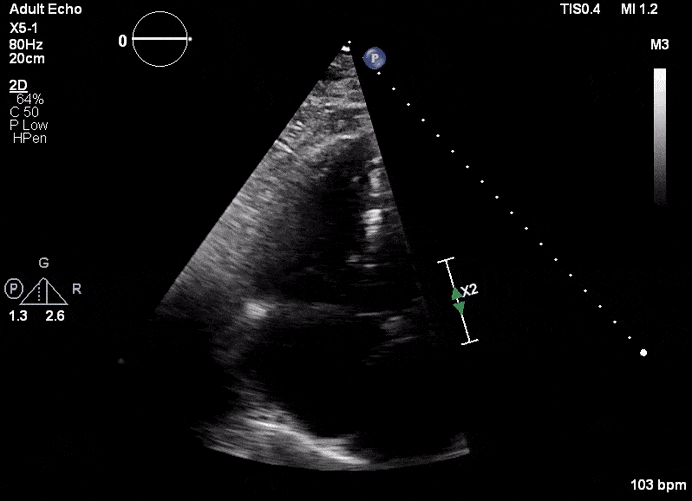

Echocardiogram

- Can be useful in assessing the severity of an RV infarct

- Visual qualitative assessment

- TAPSE (Tricuspid Annular Plane Systolic Excursion) is a validated tool to assess RV function

- Involves am M-mode at the base of the RV to assess tricuspid annular motion

- Normal ≥ 1.7 cm

- TAPSE has been validated as a predictor of heart failure and survival

- Tissue Doppler

- Systolic excursion (S’) of < 9.5 cm/sec is suggestive of RV dysfunction

RV Infarct on ECHO